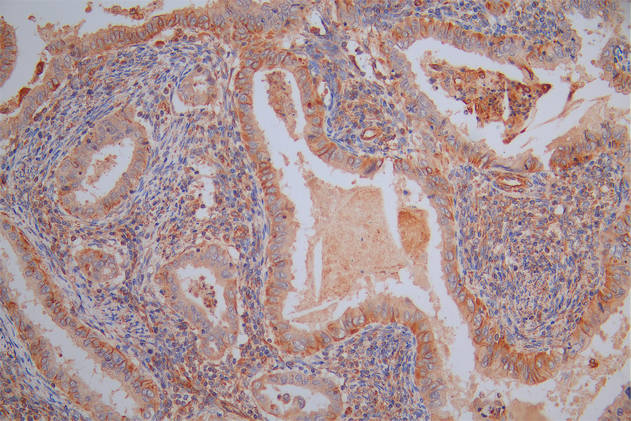

Immunohistochemistry of paraffin-embedded human kidney tissue using CSB-PA026121LA01HU at dilution of 1:100

Immunohistochemistry of paraffin-embedded human liver cancer using CSB-PA026121LA01HU at dilution of 1:100